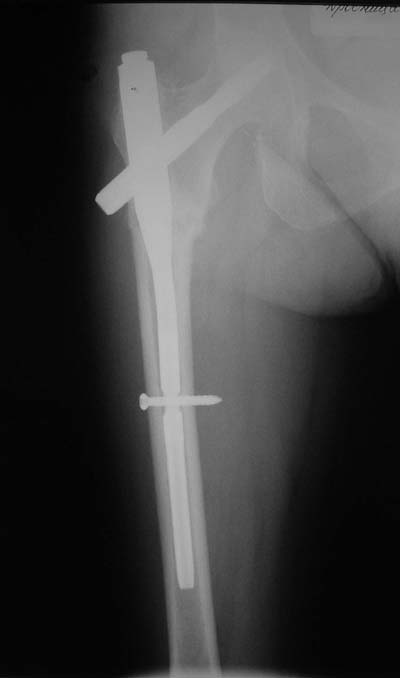

Да? Качество рентгенограмм конечно неочень, но ведь это нестабильный перелом 31.А2.2, не так ли?

Не думаю так. см вложение.

> Да? Качество рентгенограмм конечно неочень, но ведь это

> нестабильный перелом 31.А2.2, не так ли?

Ну, после помещения туда такого гвоздя даже без дистального винта заметной нестабильности уже не остается ;-)

Для такого перелома вполне может быть использован диафизарный штифт, который отечественного производства я даже боюсь считать во сколько раз дешевле... Недавно несколько примеров я закидывал.